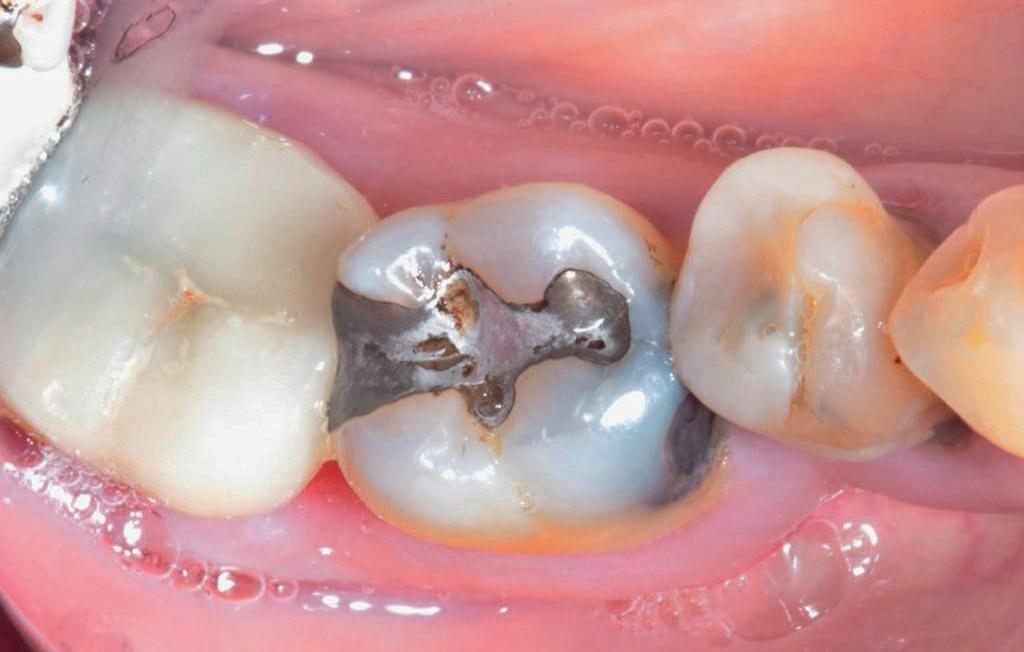

Voordat je aan een wortelkanaalbehandeling begint, zorg je voor (of maak je) een goede beginfoto waar het te behandelen gebitselement volledig op staat afgebeeld. Deze foto geeft essentiële informatie: de grootte van de pulpakamer en de ligging ervan; het aantal en de vorm van de wortels en de breedte van hun wortelkanalen en de lengte van de wortels. Hiermee kan je de DETI-score bepalen en de moeilijkheidsgraad inschatten. De grootte en de ligging van de pulpakamer op de röntgenfoto in combinatie met de ideale anatomische vorm, zoals in foto 1 is aangegeven, bepaalt de uiteindelijke vormgeving van de opening. Bij de molaren liggen de kanaalingangen in de buurt van de knobbeltoppen. Als die niet meer in originele staat

(kroon, restauratie) zijn, kan je ook de wortel gebruiken. Soms moet je net subgingivaal sonderen, maar de kanaalingang ligt in het middel van de wortel. Als je die plek visualiseert en projecteert op je opening, boor je de goede kant op. Nog een tip: wees bij het openen niet spaarzaam met het wegnemen van aanwezig restauratiemateriaal (wees wél spaarzaam met het onnodig wegnemen van tandweefsel).

De casus

De verwijzend tandarts is bezig om een wortelkanaalbehandeling uit te voeren in gebitselement 27. Er zijn vier kanalen gevonden, maar helaas breekt er in het mesiobuccale kanaal (MB 1) een WaveOne vijltje af, maat geel (foto 2). Het lukt de tandarts niet om

1. De locatie van de kanaalingangen ten opzichte van de occlusale morfologie (rood). In zwart is de ideale of standaard opening ingetekend. De uiteindelijke vorm van de opening is voorts ook afhankelijk van de klinische situatie, die vooral vanuit een goede begin foto wordt verkregen.

2. Het afgebroken instrument op de foto van de verwijzend tandarts.

3. De opening is vrij klein gekozen. In rood is de ideale opening aangegeven, de tandarts had veel meer restauratiemateriaal mogen wegnemen.

het vijltje te verwijderen. De patiënte wordt verwezen voor het afmaken van de wortelkanaalbehandeling.

Als ik de patiënte zie, valt me op dat de opening die de tandarts gemaakt heeft, nogal klein is (foto 3). Eigenlijk is daar niet zoveel reden toe; als ik een ideale opening inteken (in rood), dan loopt een groot deel door restauratiemateriaal. Overwogen kan worden om de aanwezige mesiale box met restauratiemateriaal weg te halen als dat het zicht op de pulpakamer vergroot – ik verwijs naar de tip hierboven (wees bij het openen niet spaarzaam met het wegnemen van aanwezig restauratiemateriaal).

Het afgebroken instrument ligt vrij diep; in het onderste 1/3 deel van de wortel. Vaak laten we het afgebroken instrument in het onderste 1/3 deels zitten, omdat verwijderen lastig is en er een kans is op schade. Daarom proberen we het te passeren en wordt het afgebroken instrument onderdeel van de kanaalvulling.

Passeren lukt mij in deze casus helaas niet. Omdat het instrument in een recht deel van het kanaal ligt, waag ik een poging om het afgebroken instrumentje te verwijderen, zodat ik het kanaal kan desinfecteren en kan vullen.

Onder microscopie en met een LN boortje zoek ik het instrumentje op. Na verificatie verwijder ik het door

met een ultrasone tip (Spartan CPR 8, bruin) rondom het vijltje materiaal weg te nemen, waardoor deze als het ware uitgegraven wordt. WaveOne vijltjes zijn irritant om te verwijderen, het nikkeltitanium materiaal wil naar een oorspronkelijke vorm (een rechte vorm) terugbuigen en daarom drukt het zich steeds vast bij het verwijderen. Staal is vaak makkelijker te verwijderen. Maar het lukt me en de wortelkanaalbehandeling kan worden afgemaakt.

Het verwijderen van een afgebroken instrument kost altijd relatief veel (gezond) tandweefsel en kent veel risico op perforatie of andere schade. Daarom is het altijd belangrijk om goed te overwegen of een vijl verwijderd moet worden.

Maar beter nog is om te voorkomen dat een vijltje afbreekt door bij de opening voldoende te prepareren voor goed zicht en voor wat we noemen een ‘straight line access’. Goede voorbereiding is het halve werk.